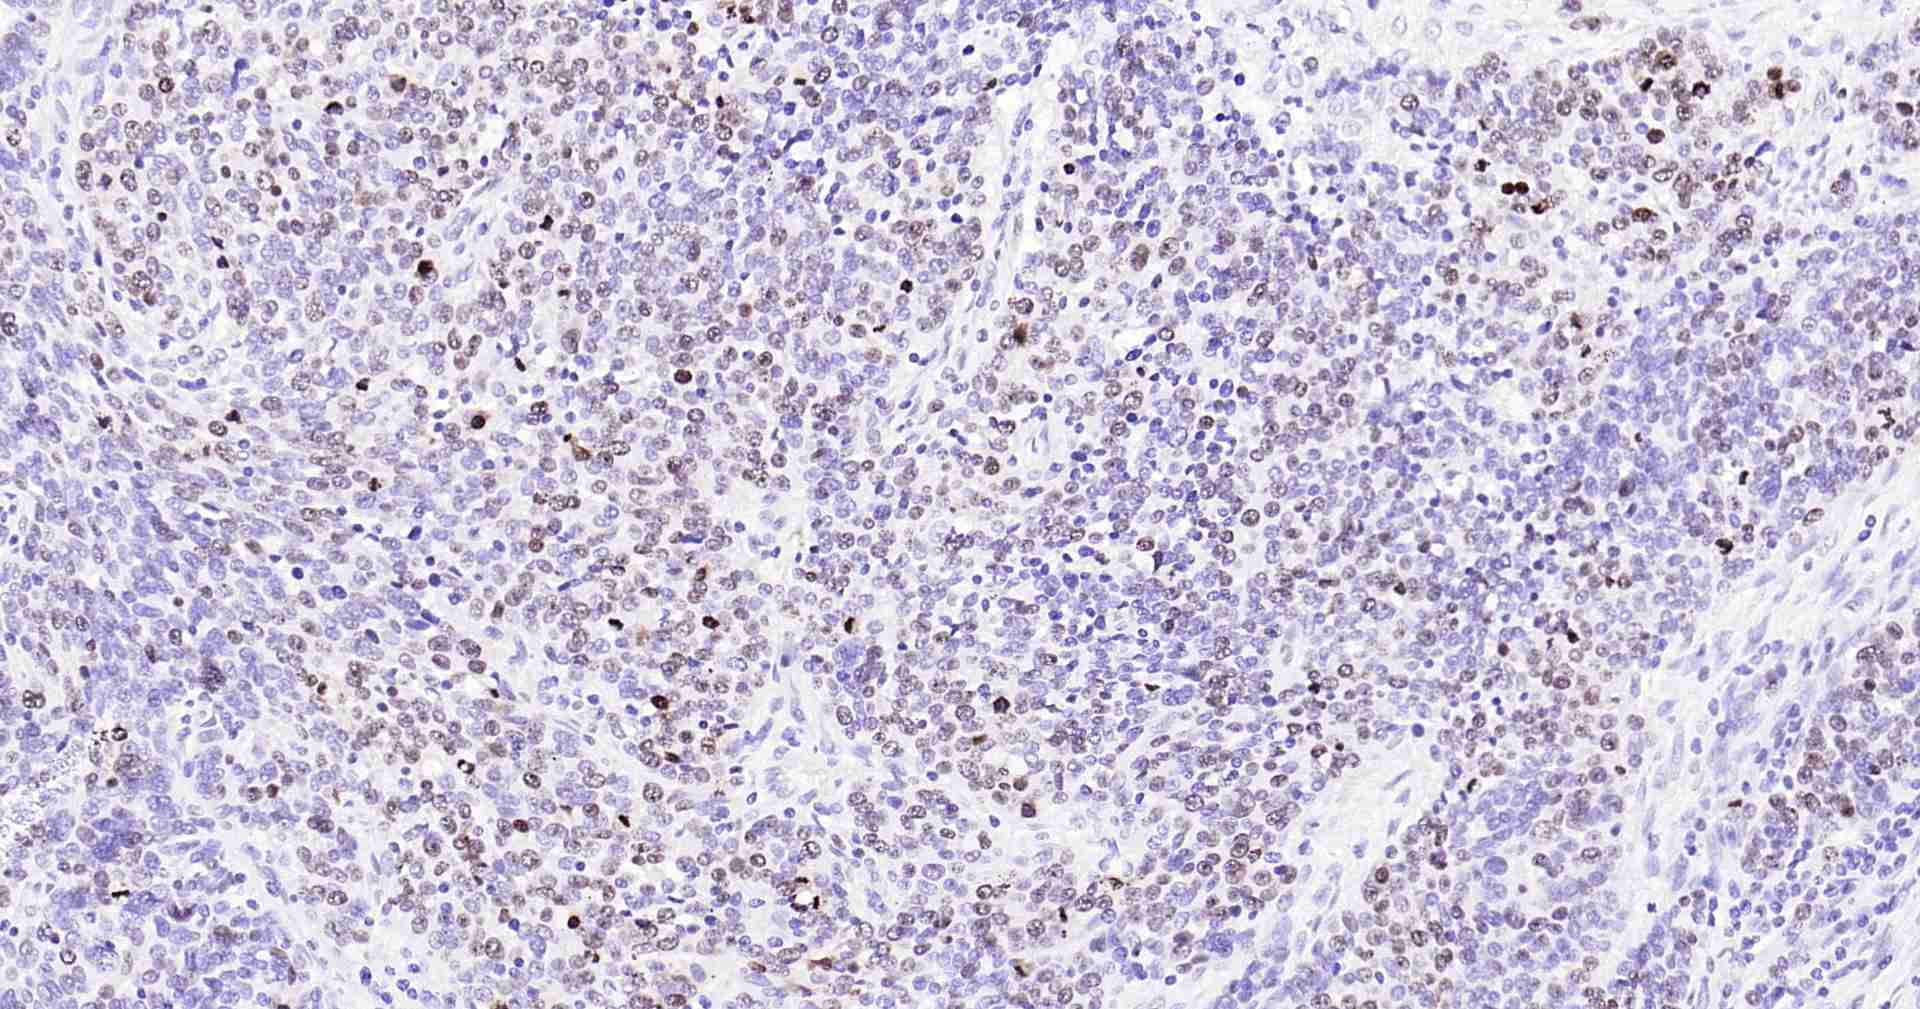

Immunohistochemical analysis of paraffin embedded human serous ovarian carcinoma tissue slide using IHC0246H (Human ki-67 IHC Kit).

Immunohistochemical analysis of paraffin embedded human colon cancer tissue slide using IHC0246H (Human ki-67 IHC Kit).

Immunohistochemical analysis of paraffin embedded human tonsil tissue slide using IHC0246H (Human ki-67 IHC Kit).